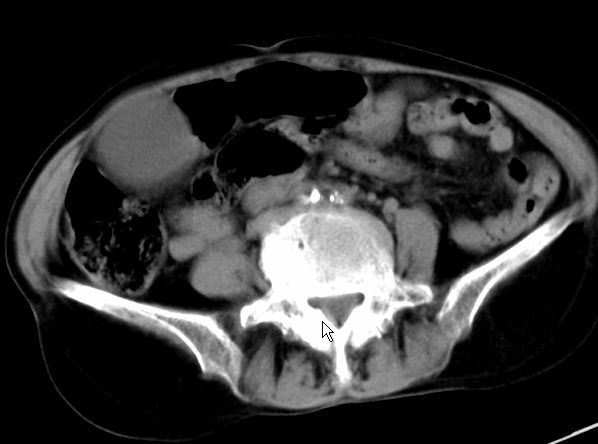

以下是引用zjzjr在2008-12-16 12:49:00的发言:[br]肝内外胆管全程扩张,胆囊明显增大,未见占位征像.建议mrcp.

以下是引用jiangjing在2008-12-16 13:19:00的发言:[br]肝内外胆管全程扩张,胆囊明显增大,扩张胆总管下段径较中上段小,未见胰管扩张,提示胆总管远端梗阻伴感染.建议增强及mrcp 检查

以下是引用朱亮在2008-12-16 12:54:00的发言:[br]胆总管远端应薄层扫描 胆总管逐渐变细 考虑胆系慢性炎症